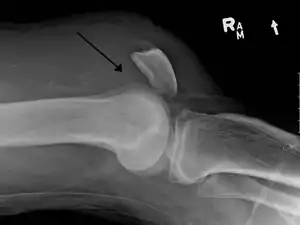

Operative image: 1. Kneecap 2. upper patella pole with drill holes 3. Stump of the quadriceps tendon